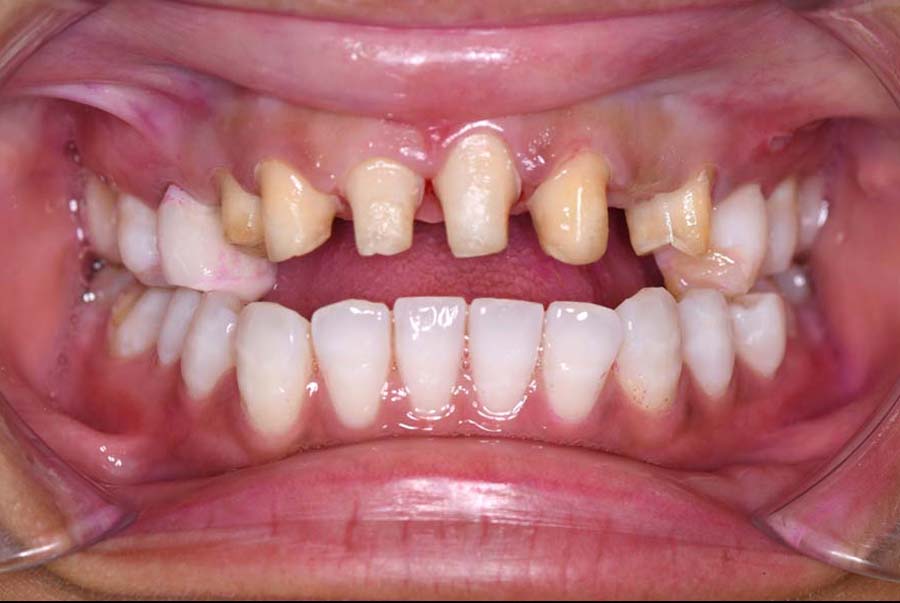

主訴 噛み合わせが悪い

初診日 2023年10月12日

2024年 3月 初診時

2024年 10月10日